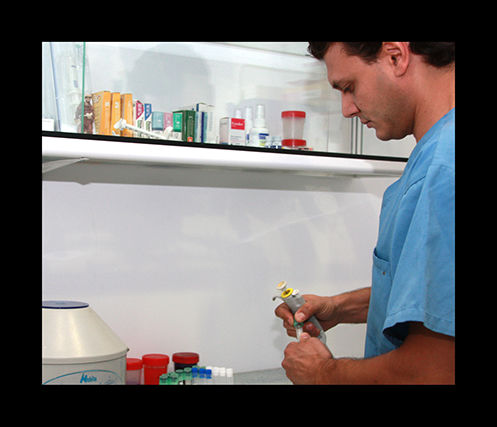

análisis clínicos

En clinican contamos con un laboratorio donde podemos realizar análisis de sangre, orina…